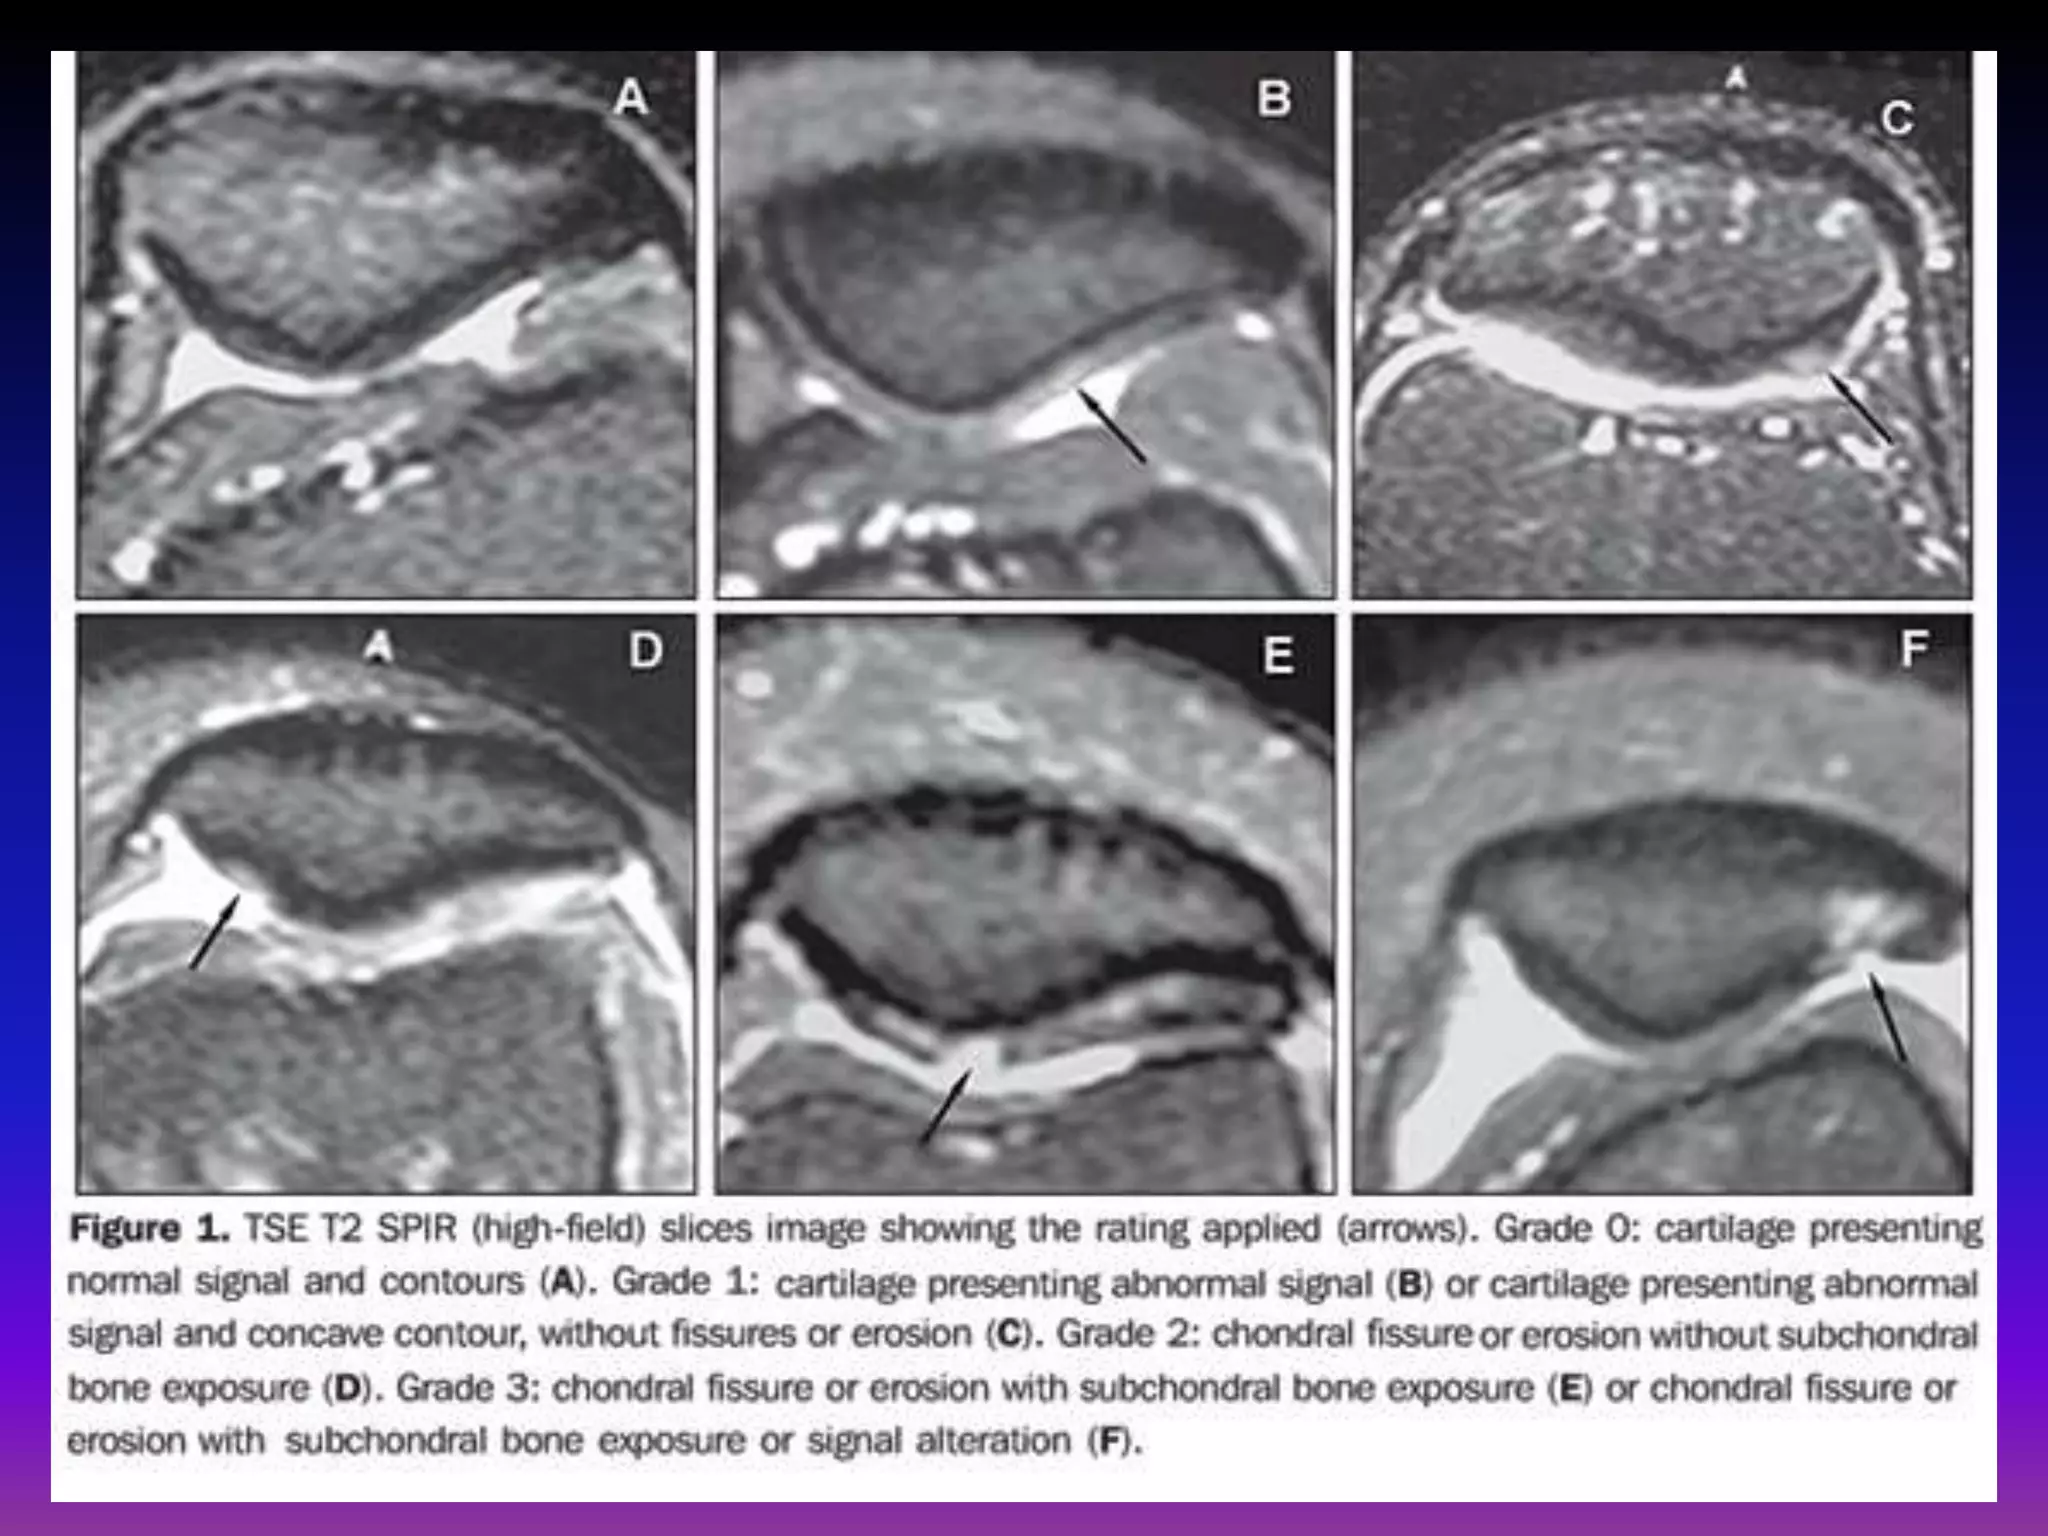

Chondromalacia can be divided into 4 grades by MRI, typically using fat

saturated proton density sequences. This grading system is the modified

outer bridge grading system, which was devised for arthroscopy initially for

assessment of chondromalacia patella, but then modified and extended for

all chondral surfaces.

grade I.

Focal areas of hyperintensity with normal contour

arthroscopically : softening or swelling of cartilage.

grade II.

Blister-like swelling/ fraying of articular cartilage extending to surface

arthroscopically : fragmentation and fissuring within soft areas of

articular cartilage.

grade III.

Partial thickness cartilage loss with focal ulceration

arthroscopically : partial thickness cartilage loss with fibrillation (crab-

meat appearance).

grade IV.

Full thickness cartilage loss with underlying bone reactive changes

arthroscopically : cartilage destruction with exposed subchondral bone.